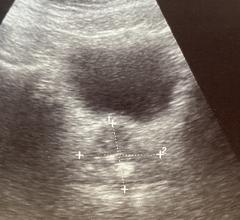

Prostate Cancer

News and new technology innovations concerning how imaging technology can help diagnose and treat prostate cancer can be found on this channel.